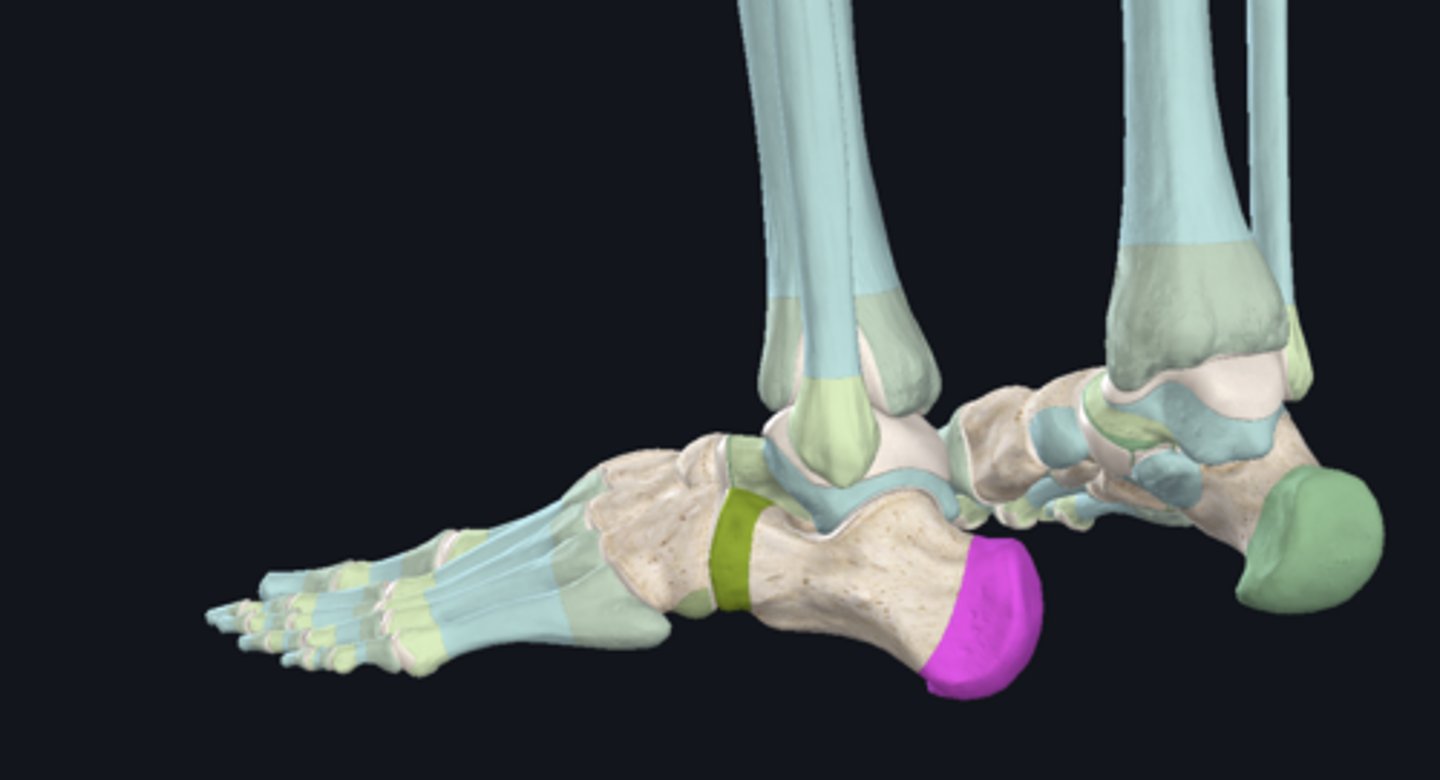

Calcaneus

Calcaneal tuberosity for triceps surae (gastrocnemius and soleus) tendon

Sustentaculum tali (medial shelf for talus)

Posterior talar articular surface

Middle talar articular surface

Anterior talar articular surface

Articular surface for cuboid bone

Talus

Superior trochlear surface

Plantar aponeurosis